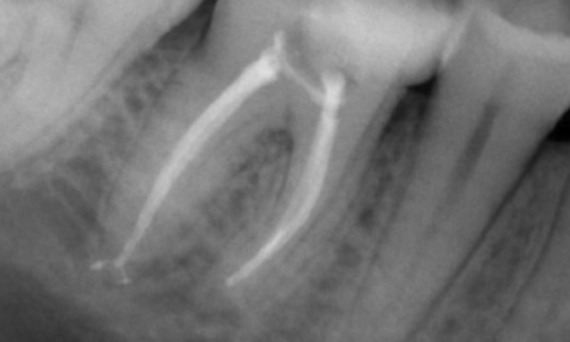

Przed: Podczas badania stwierdzono zmianę próchnicową związaną z dolnym prawym pierwszym trzonowcem. Badanie radiologiczne wykazało bliskość zmiany do rogu miazgi. Łącząc to z główną skargą pacjenta, postawiono ostateczną diagnozę przewlekłego nieodwracalnego zapalenia miazgi.

Po: Dostęp do ubytku został wykonany tak zachowawczo, jak to tylko możliwe. System TruNatomy został wybrany ze względu na młody wiek pacjenta. Musieliśmy zachować zębinę w jak największym stopniu, aby zwiększyć zdolność zęba do pokonywania obciążeń okluzyjnych i zwiększyć trwałość ostatecznej odbudowy.